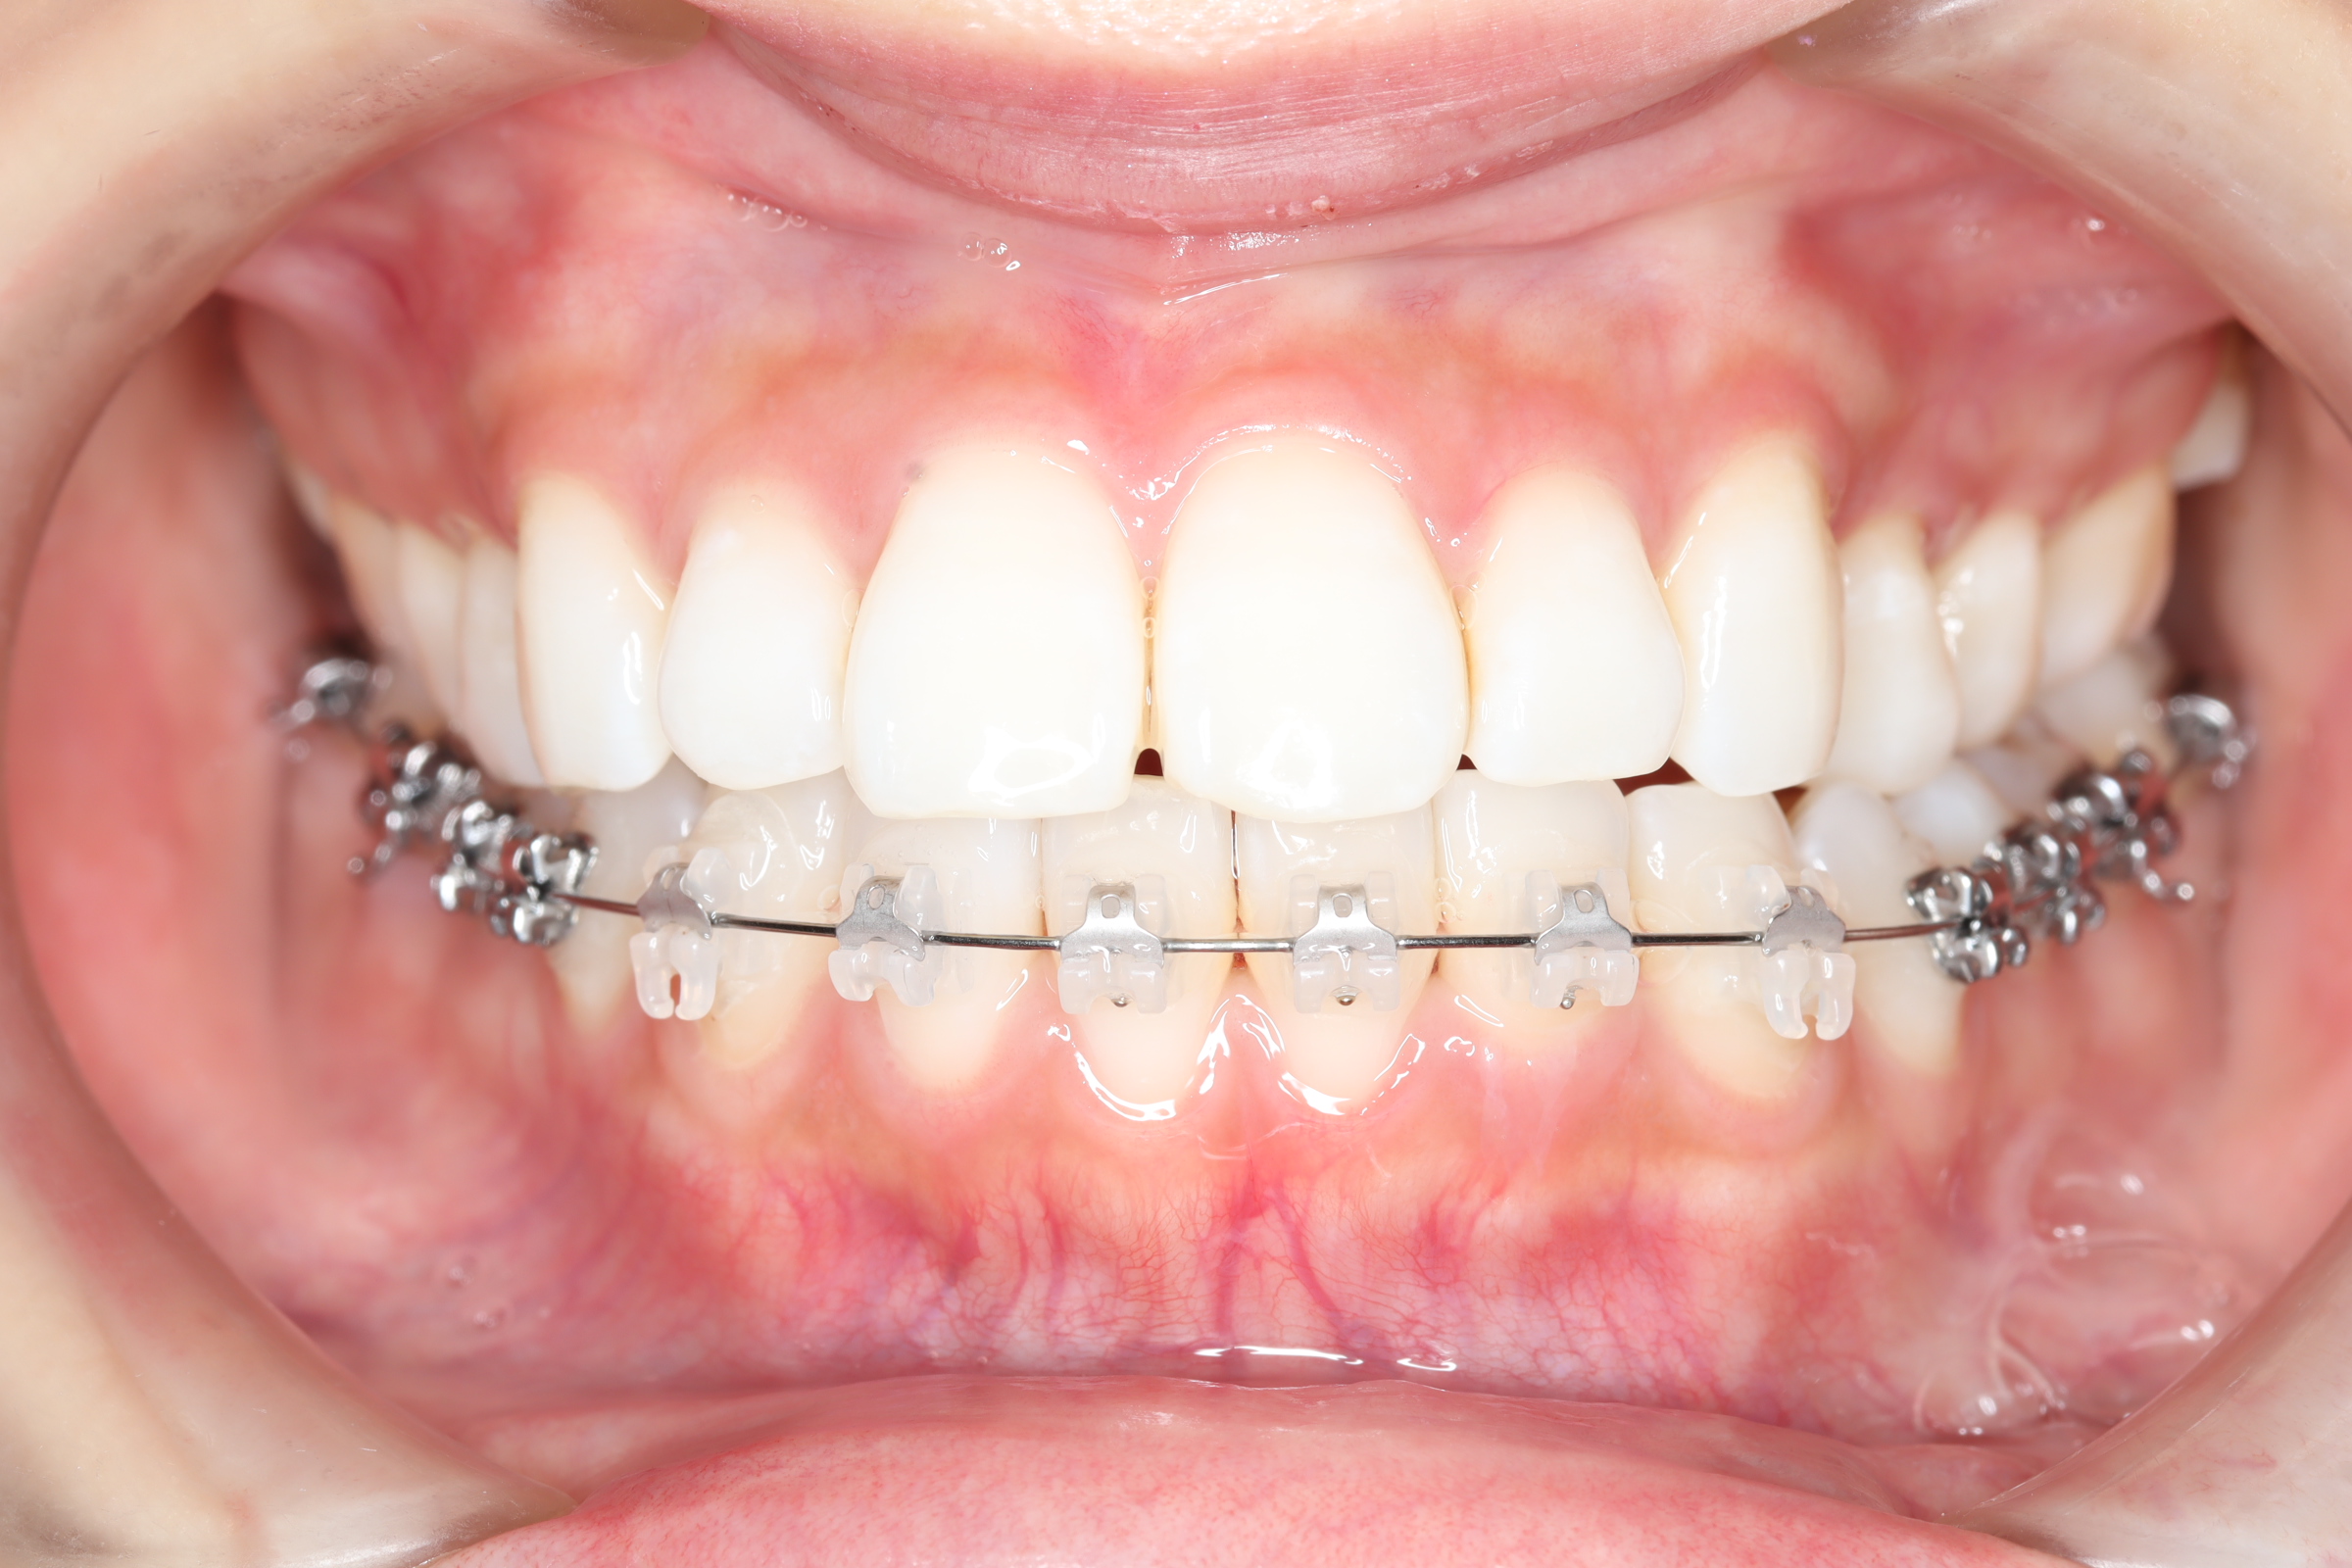

治療中

![]() | ||

![]() | ![]() | ![]() |

| 使用矯正装置 | 上顎:セルフライゲーションリンガルブラケット 下顎:セルフライゲーションブラケット(セラミッククリッピー) 歯科矯正用アンカースクリュー |